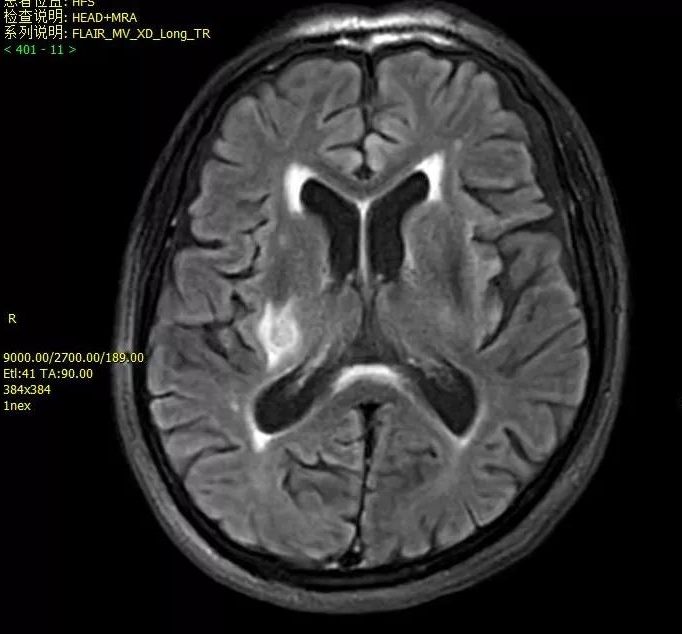

- 头颅MR平扫即颅脑磁共振成像检查,是一种利用磁场和射频脉冲使人体组织内进动的氢核发生章动产生信号,经计算机处理而成像的技术。无需注射造影剂,就能清晰地显示脑组织的形态、结构和信号特征。

- 相比于传统的CT检查,MRI对脑内结构的显示更加清晰,能够更早地发现病变,特别是CT难以发现的微小病变,如脑脱髓鞘性病变、脑炎、感染性病变以及早期缺血性病变等。此外,MRI还具有无创伤、无辐射、对脑组织无损伤等优点。

- DWI是一种能够反映水分子弥散运动特性的成像技术,在脑梗死超早期,由于脑细胞急性缺血缺氧,细胞毒性水肿导致水分子弥散受限,DWI序列上即可显示出高信号。此外,DWI在诊断脑脓肿、肿瘤、脱髓鞘疾病等方面也具有一定的价值。